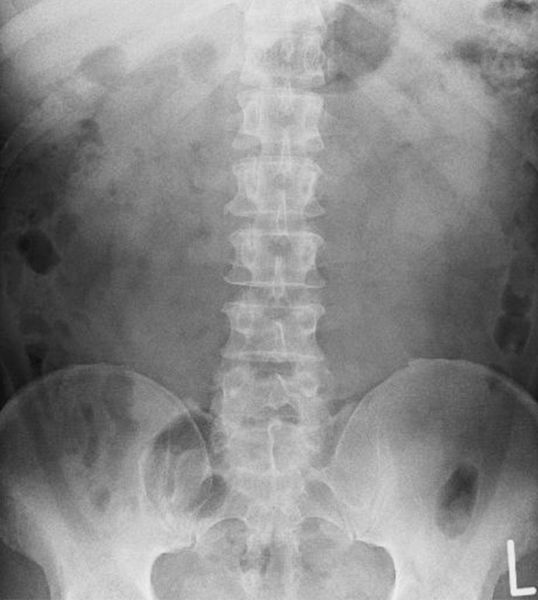

椎間板ヘルニアが「見える腰痛」といわれる理由として画像検査のMRIやレントゲンに映っているので診察の判断でき、原因が“見える形”で原因を特定できる数少ない腰痛の1つだからです。

レントゲンなどで診断できる腰痛

■1. 変形性腰椎症(腰椎の老化・変形)

・椎体の変形・骨棘(棘状の外骨腫)・椎間板のの狭さ

■2. 腰椎すべり症

椎骨が前後にずれる症状

大きく「変性すべり症」「分離すべり症」の2種類

■3. 腰椎分離症

激しいスポーツや部活などでなることが多く、椎弓にひび(疲労骨折)が入る状態でレントゲンで欠損が確認できます。